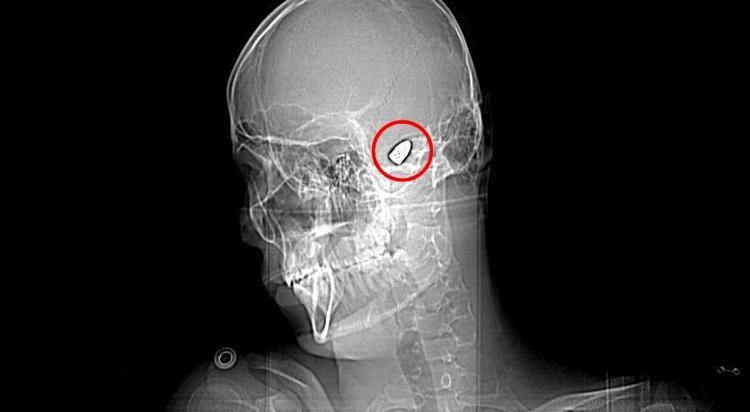

Olay, 5 Kasım 2023’te Bahçelievler Mahallesi 1624'üncü Sokak'ta meydana geldi. Arkadaşları ve ağabeyiyle maça gitmek için evinden çıkan Yusuf Emre Özbek, birlikte fotoğraf çektirdikten hemen sonra yere yığıldı. Çevredekilerin hastaneye götürdüğü Yusuf’un çekilen röntgeninde, başında mermi çekirdeği olduğu tespit edildi.

4 gün yoğun bakım, 4 gün de serviste tedavi gören Yusuf’un başındaki mermi için doktorlar, riskli bölgede olduğu gerekçesiyle müdahale etmedi. Düzenli olarak kontrol edilen Yusuf’ta konuşma güçlüğü ve sağ el ve parmaklarında zayıflık belirtileri ortaya çıkınca, fizik tedavi süreci başladı.